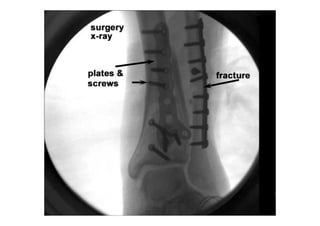

RADIOLOGIA DO

TRAUMA DO ESQUELETO

Referência: http://www.accessexcellence.org/RC/VL/